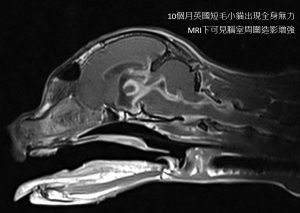

神經型FIP需要經過核磁共振(MRI)評估腦部結構,並採取腦脊髓液(CSF)才能獲得確實診斷。